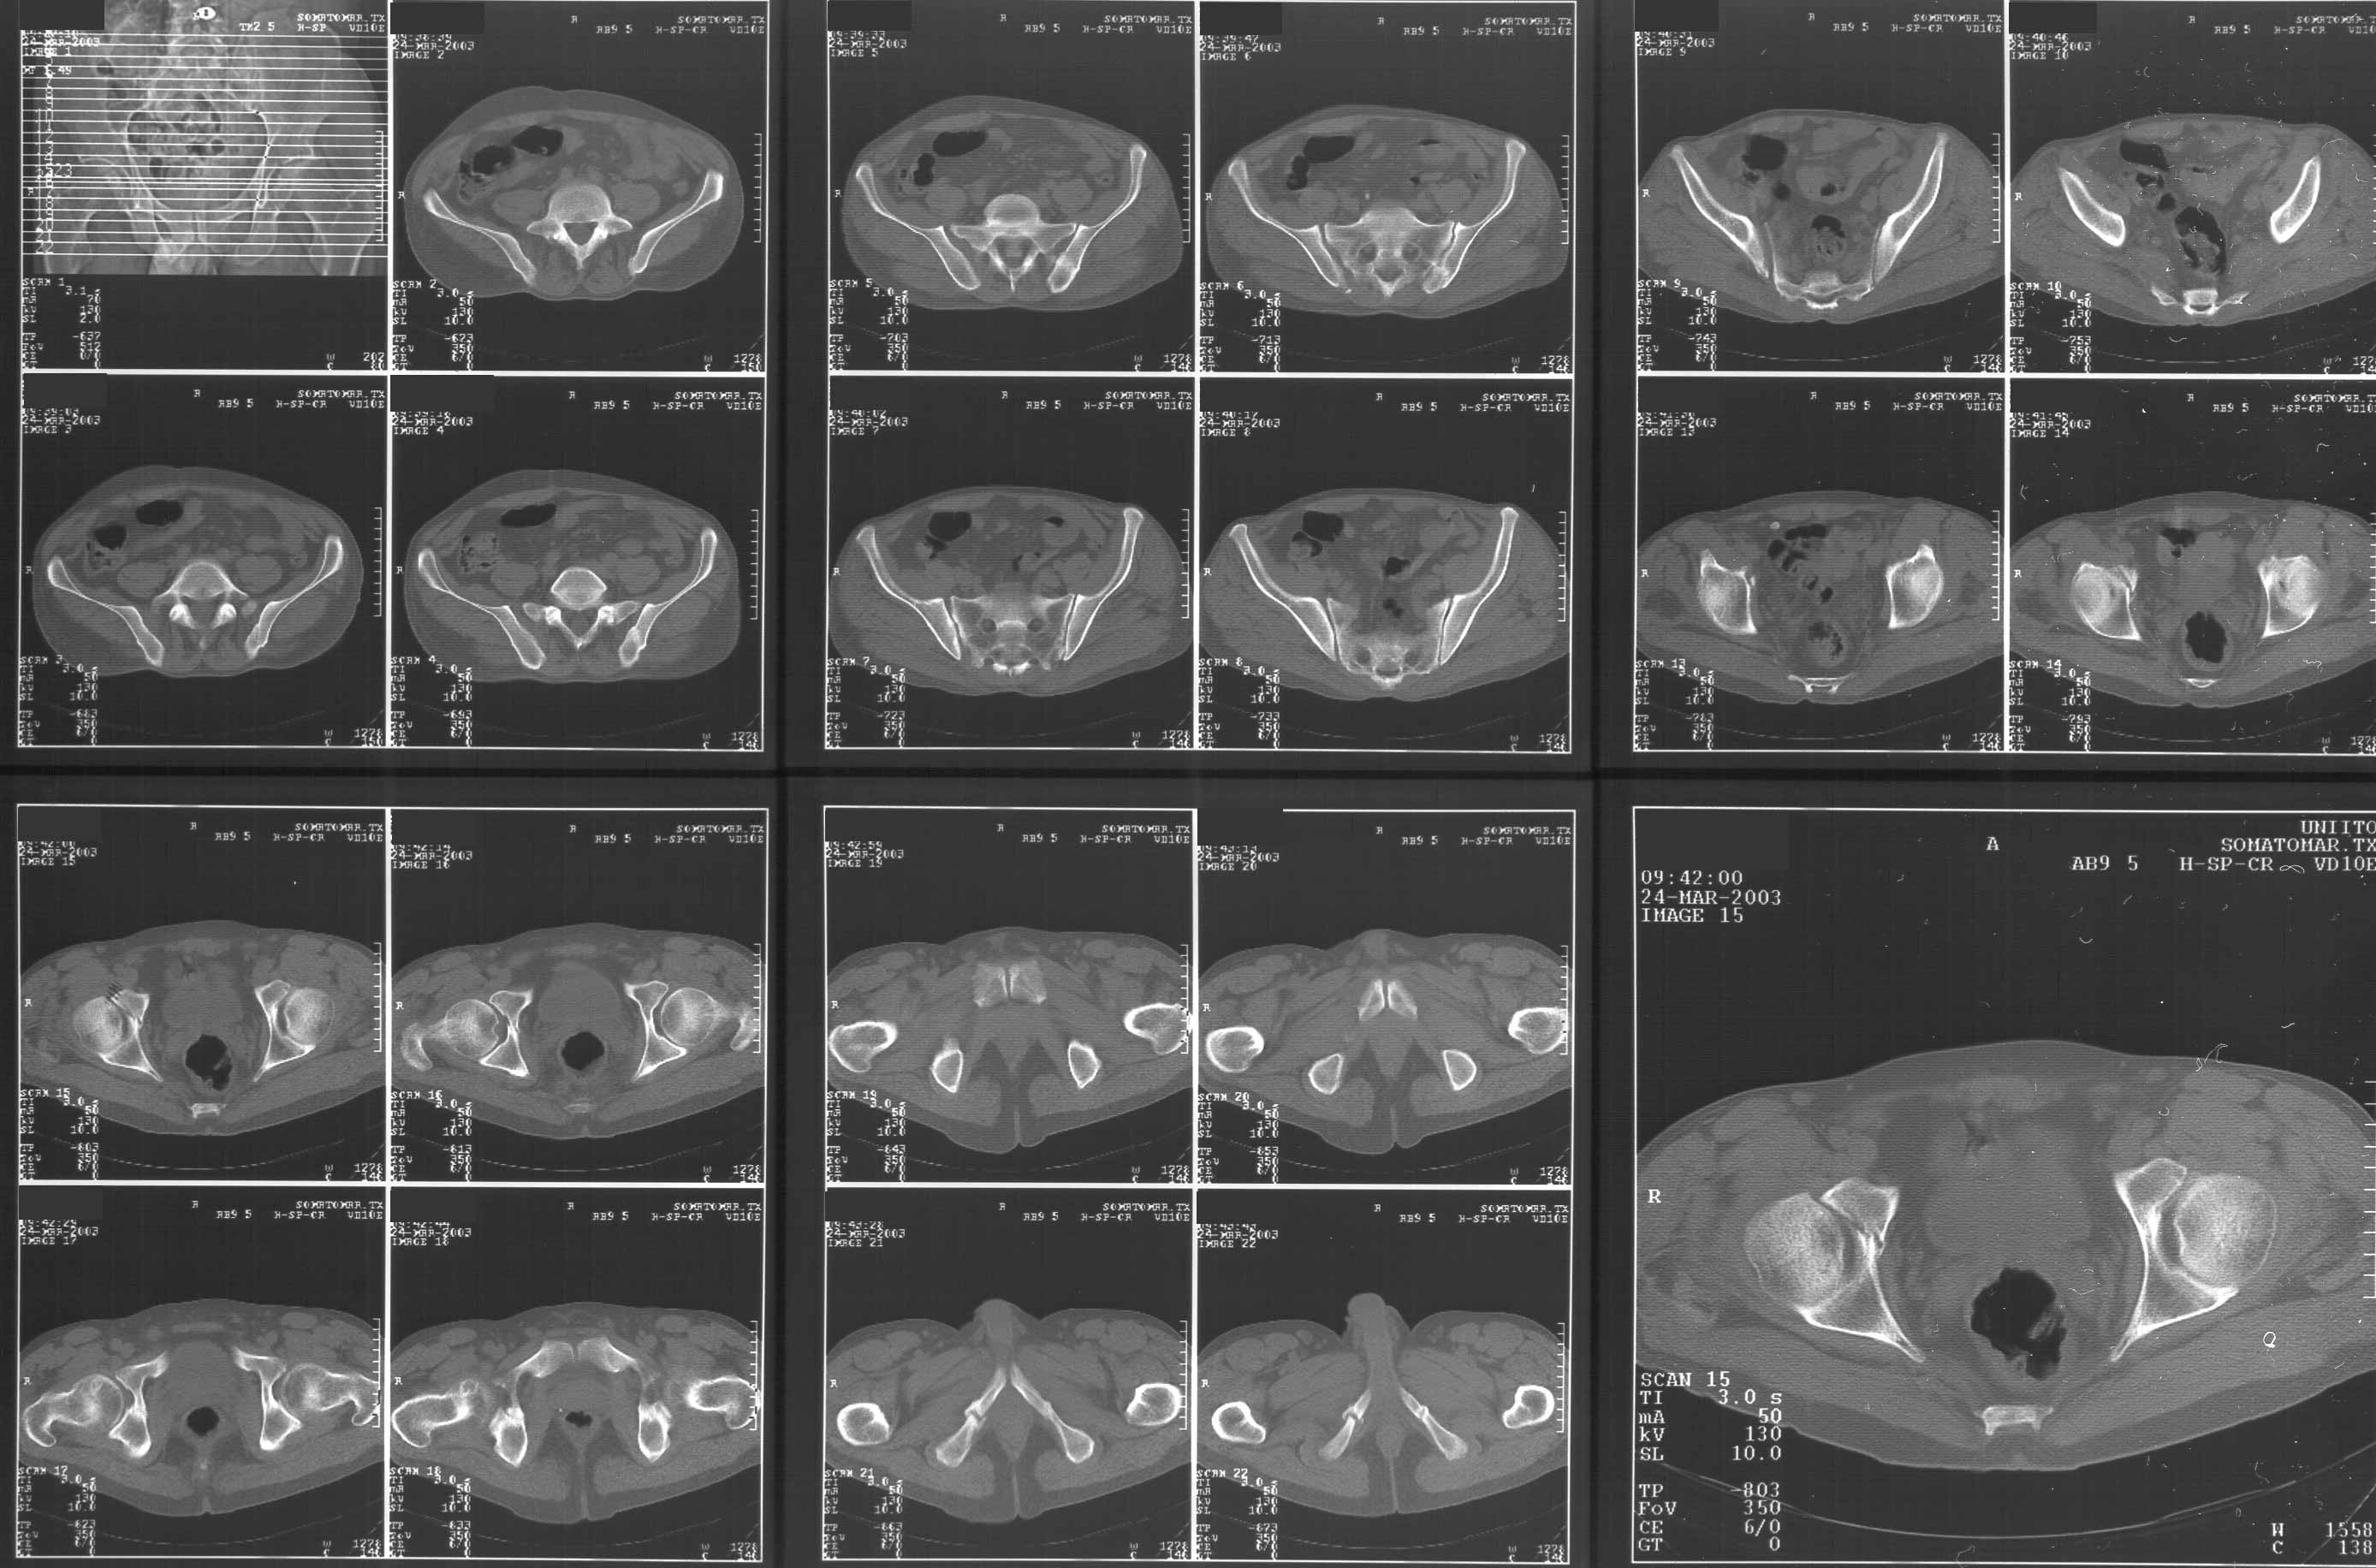

CR> A pelvic CT scan.

Attached. I may upload the one with larger resolution.

Based on the CT images you provided, he appears to have a nonunion of the the right ischium, which would explain his symptoms. General principles of treatment of hypertrophic (which this appears to be) nonunions suggest rigid fixation, but I'm not sure what the best approach would be. Could get a lag screw across the fracture through a Kocher-Langenbeck approach or plate osteosynthesis through direct ischial approach, but perhaps Chip, Adam or someone with more pelvic fracture experience could enlighten us all.

I didn't see it on the images...maybe I need glasses!!

I'll try to enlarge the images to understand.

I didn't see it either - can anybody re-send me the CT images?

I think the cuts in question (albeit small) are on the right of the bottom row of the CT scan

I think this is just a pelvic ring disruption that has gone on to a non-union. The arrow is pointing to the inferior ramus non-union, and the sup ramus is a high "root" fracture, right near the pecten. The sup ramus fracture enters the tab - you could call it an acetabular fracture - but down here in Dallas we treat these acutely as stable pelvic ring injuries. The fracture in the anterior portion of the acetabulum is so low it doesn't seem to cause much trouble.

His R sacroiliac joint is opened anteriorly a little bit - the "unreduced posterior lesion" Alex mentioned in his first post. My earlier post about plating, bone grafting, etc., is all wrong.

What you have is a pelvic fracture that hasn't healed after 4 months or so, with a minimal deformity.

I think what I would offer the guy is a percutaneous iliosacral screw to stabilize and improve the SI joint alignment, coupled with a perc anterior column screw to stabilize the high ramus fx. These screws aren't easy to place, and have a host of potential problems and complications. But, I think they would work.

The open treatment options carry more morbidity, in my opinion, but they could achieve the same result. It's possible to do an ilioinguinal approach and stabilize both fractures. Bone grafting of each site (you would probably aim for a fusion of the SI joint if you chose the open route) and plate fixation would likely lead to union.

The perc screw method would also likely lead to union, but with less surgical dissection. The problem with the perc method is that it requires an expert fluoroscopy technician, and a surgeon who understands the anatomy, as seen on fluoro. It's hard to do.